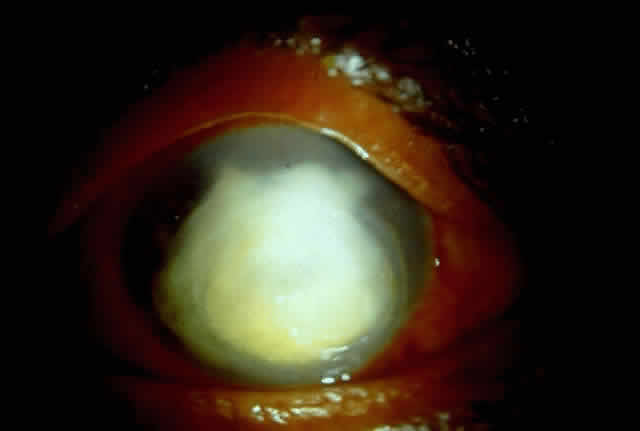

Fungal keratitis is as frequently seen as bacterial keratitis. Aspergillus and Fusarium are the two most commonly isolated organisms. Predisposing factors include trauma, foreign body, and injudicious usage of topical steroids or other indigenous medications.

Delay in diagnosis, the relative ineffectiveness of antifungal agents in most parts of the world, and the nonavailability of these drugs hinder prevention and management (Fig. 3).

Fig. 3. Advanced stage of corneal ulcer caused by Fusarium solani.